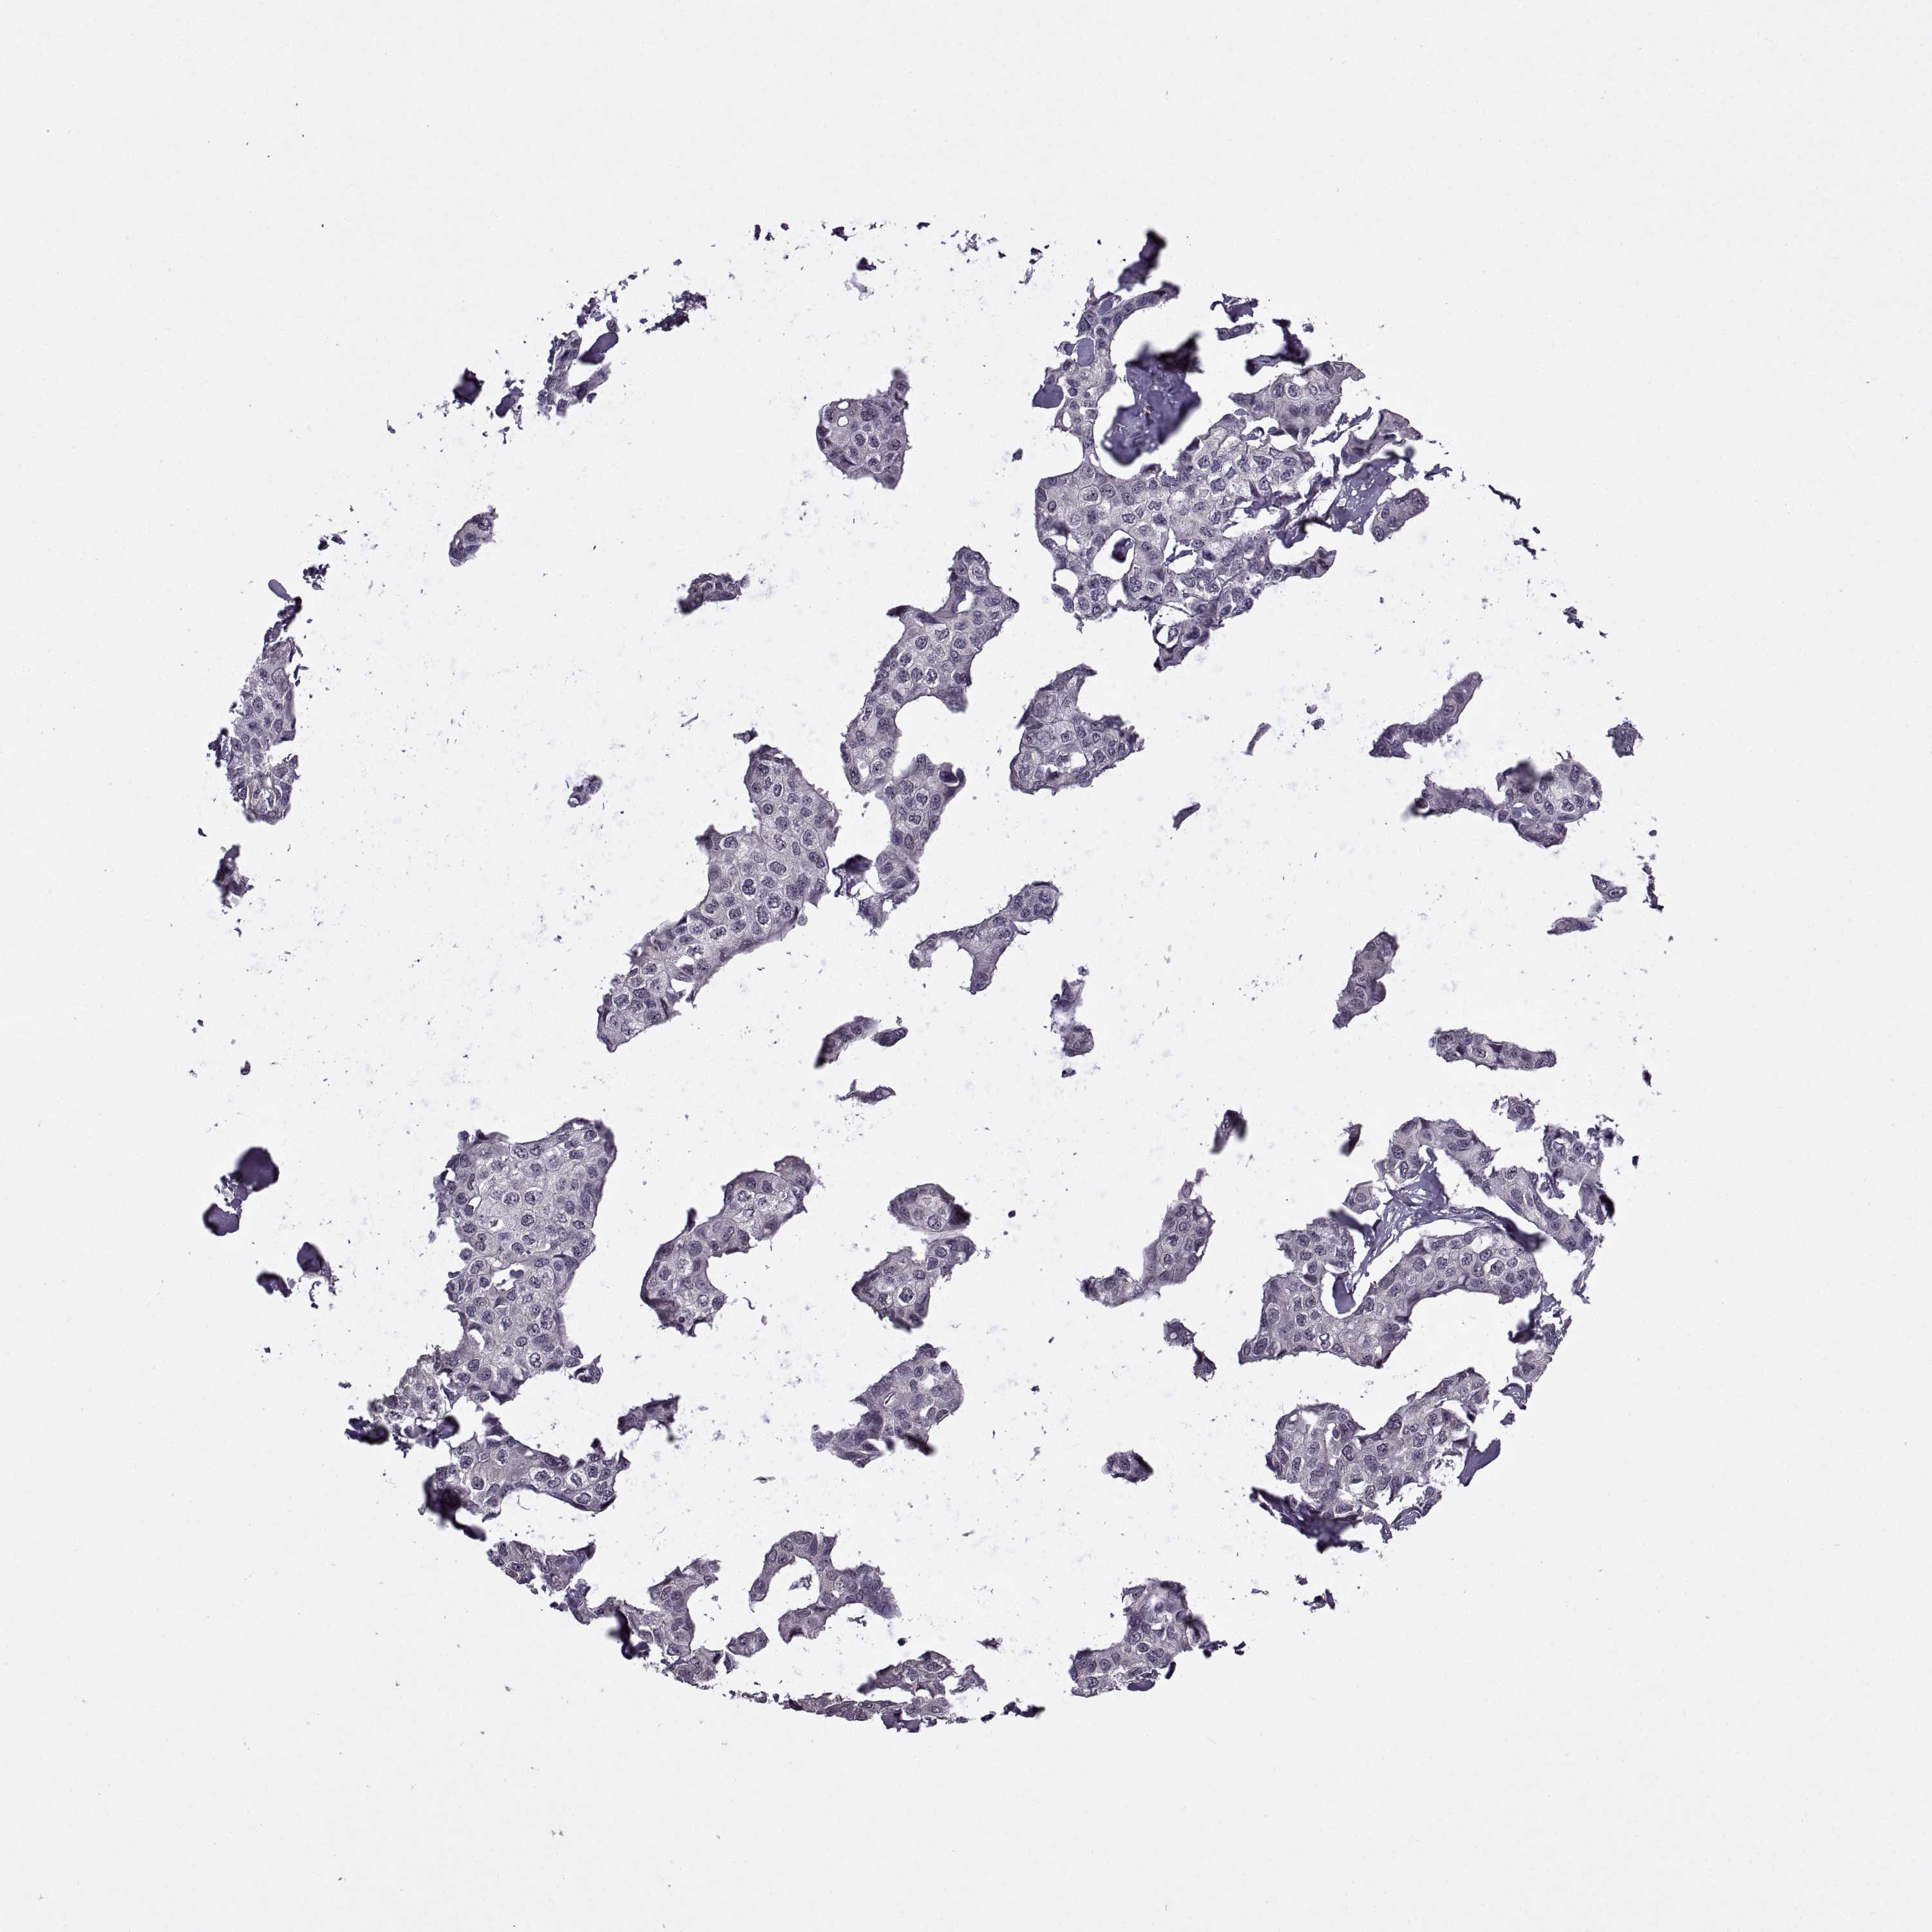

CANCER BREAST CANCER Show tissue menu

Breast cancer

Human cancer